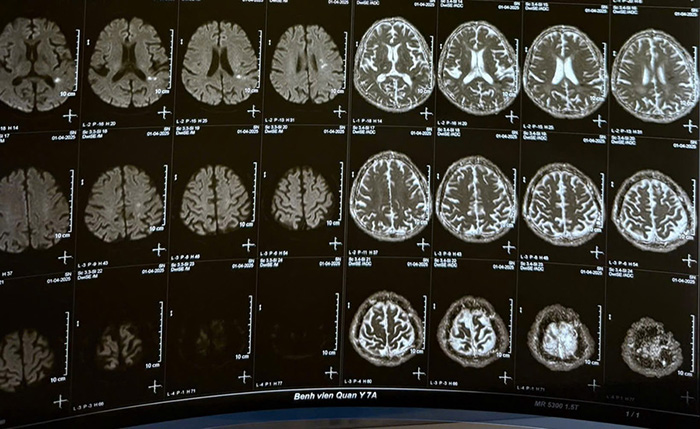

PGS.TS.BS Nguyễn Huy Thắng – Phó Chủ tịch Hội Đột quỵ Việt Nam, Chủ tịch Hội Đột quỵ TP.HCM – chia sẻ một trường hợp khiến giới chuyên môn không khỏi xót xa: Một bệnh nhi 14 tuổi, học sinh một trường THCS vốn hoàn toàn khỏe mạnh, đột ngột yếu liệt nửa người trái. Gia đình lập tức đưa em đến Trung tâm Y tế huyện gần nhà, cách TP.HCM khoảng 20km.

Tại đây, bác sĩ nghi ngờ đột quỵ và chuyển lên bệnh viện tỉnh cách đó 5km. Sau khi chụp CT và xác định đúng bệnh, bệnh viện tỉnh mới tiếp tục chuyển em đến Bệnh viện Nhân dân 115 ở TP.HCM – cách thêm 27km nữa. Khi đến nơi, em đã chết não, không thể can thiệp điều trị.

Theo BS.CKII Kiều Mạnh Hà – Chủ nhiệm Khoa Thần kinh, Bệnh viện Quân y 7A (TP.HCM), có đến 90% bệnh nhân đột quỵ mang theo các yếu tố nguy cơ có thể dự phòng. Đó là tăng huyết áp, tiểu đường, béo phì, rối loạn mỡ máu, lối sống thiếu vận động, hút thuốc lá, lạm dụng rượu bia, căng thẳng kéo dài…